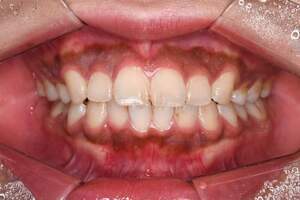

歯石除去

治療前

治療後

| 年齢 | 31歳・女性 |

| 主訴 | 主訴:歯石除去 部位:全顎 |

| 治療内容 | 初診検査・歯石除去 |

| 治療期間 | 2週間 |

| 費用 | 合計:約4,000~5,000円 内訳 初診料:約3,000~4,000円 (保険診療) 歯石除去:約1,000円 (2023年1月現在) |

| リスク・副作用 | ・歯肉の炎症がある場合は歯石除去中に出血を伴う可能性があります。 ・処置後に歯がしみることがあります。 ・歯茎の炎症が軽減すると歯茎が引き締まり、歯が長く見えることがあります。 |

| 治療方針 | 前歯部に叢生(歯列不正)があり多量の歯石が認められました。炎症の抑制を優先するため初診時はTBIのみ行い、2回目以降で歯石除去を行いました。今後は縁下歯石(歯ぐきの中に付着する歯石)の除去を全顎的に行っていく予定です。 |

| 担当者所見 | 叢生(そうせい)とは歯が折り重なるようにデコボコにはえている状態をいいます。歯ブラシが難しく磨き残しをしやすい為、普段使用している歯ブラシに加えワンタフトという細かい部分も磨くことのできる小さな毛束の歯ブラシの使用をおすすめしました。 |

| 担当者所見 | 歯石の存在は感じていたものの歯科医院に苦手意識が強く3年ほど放置していたとのことでした。 舌で触った時にザラザラすることや口臭も気になった為、今回意を決してご来院くださいました。 ブラッシング指導を熱心に聞いてくださり、セルフケアで歯肉の炎症を抑えた上で歯石除去ができたのでお痛みが少なく行えました。 患者様も苦手意識が克服できたと喜んでくださり、今後の治療にも積極的な姿勢です。 |